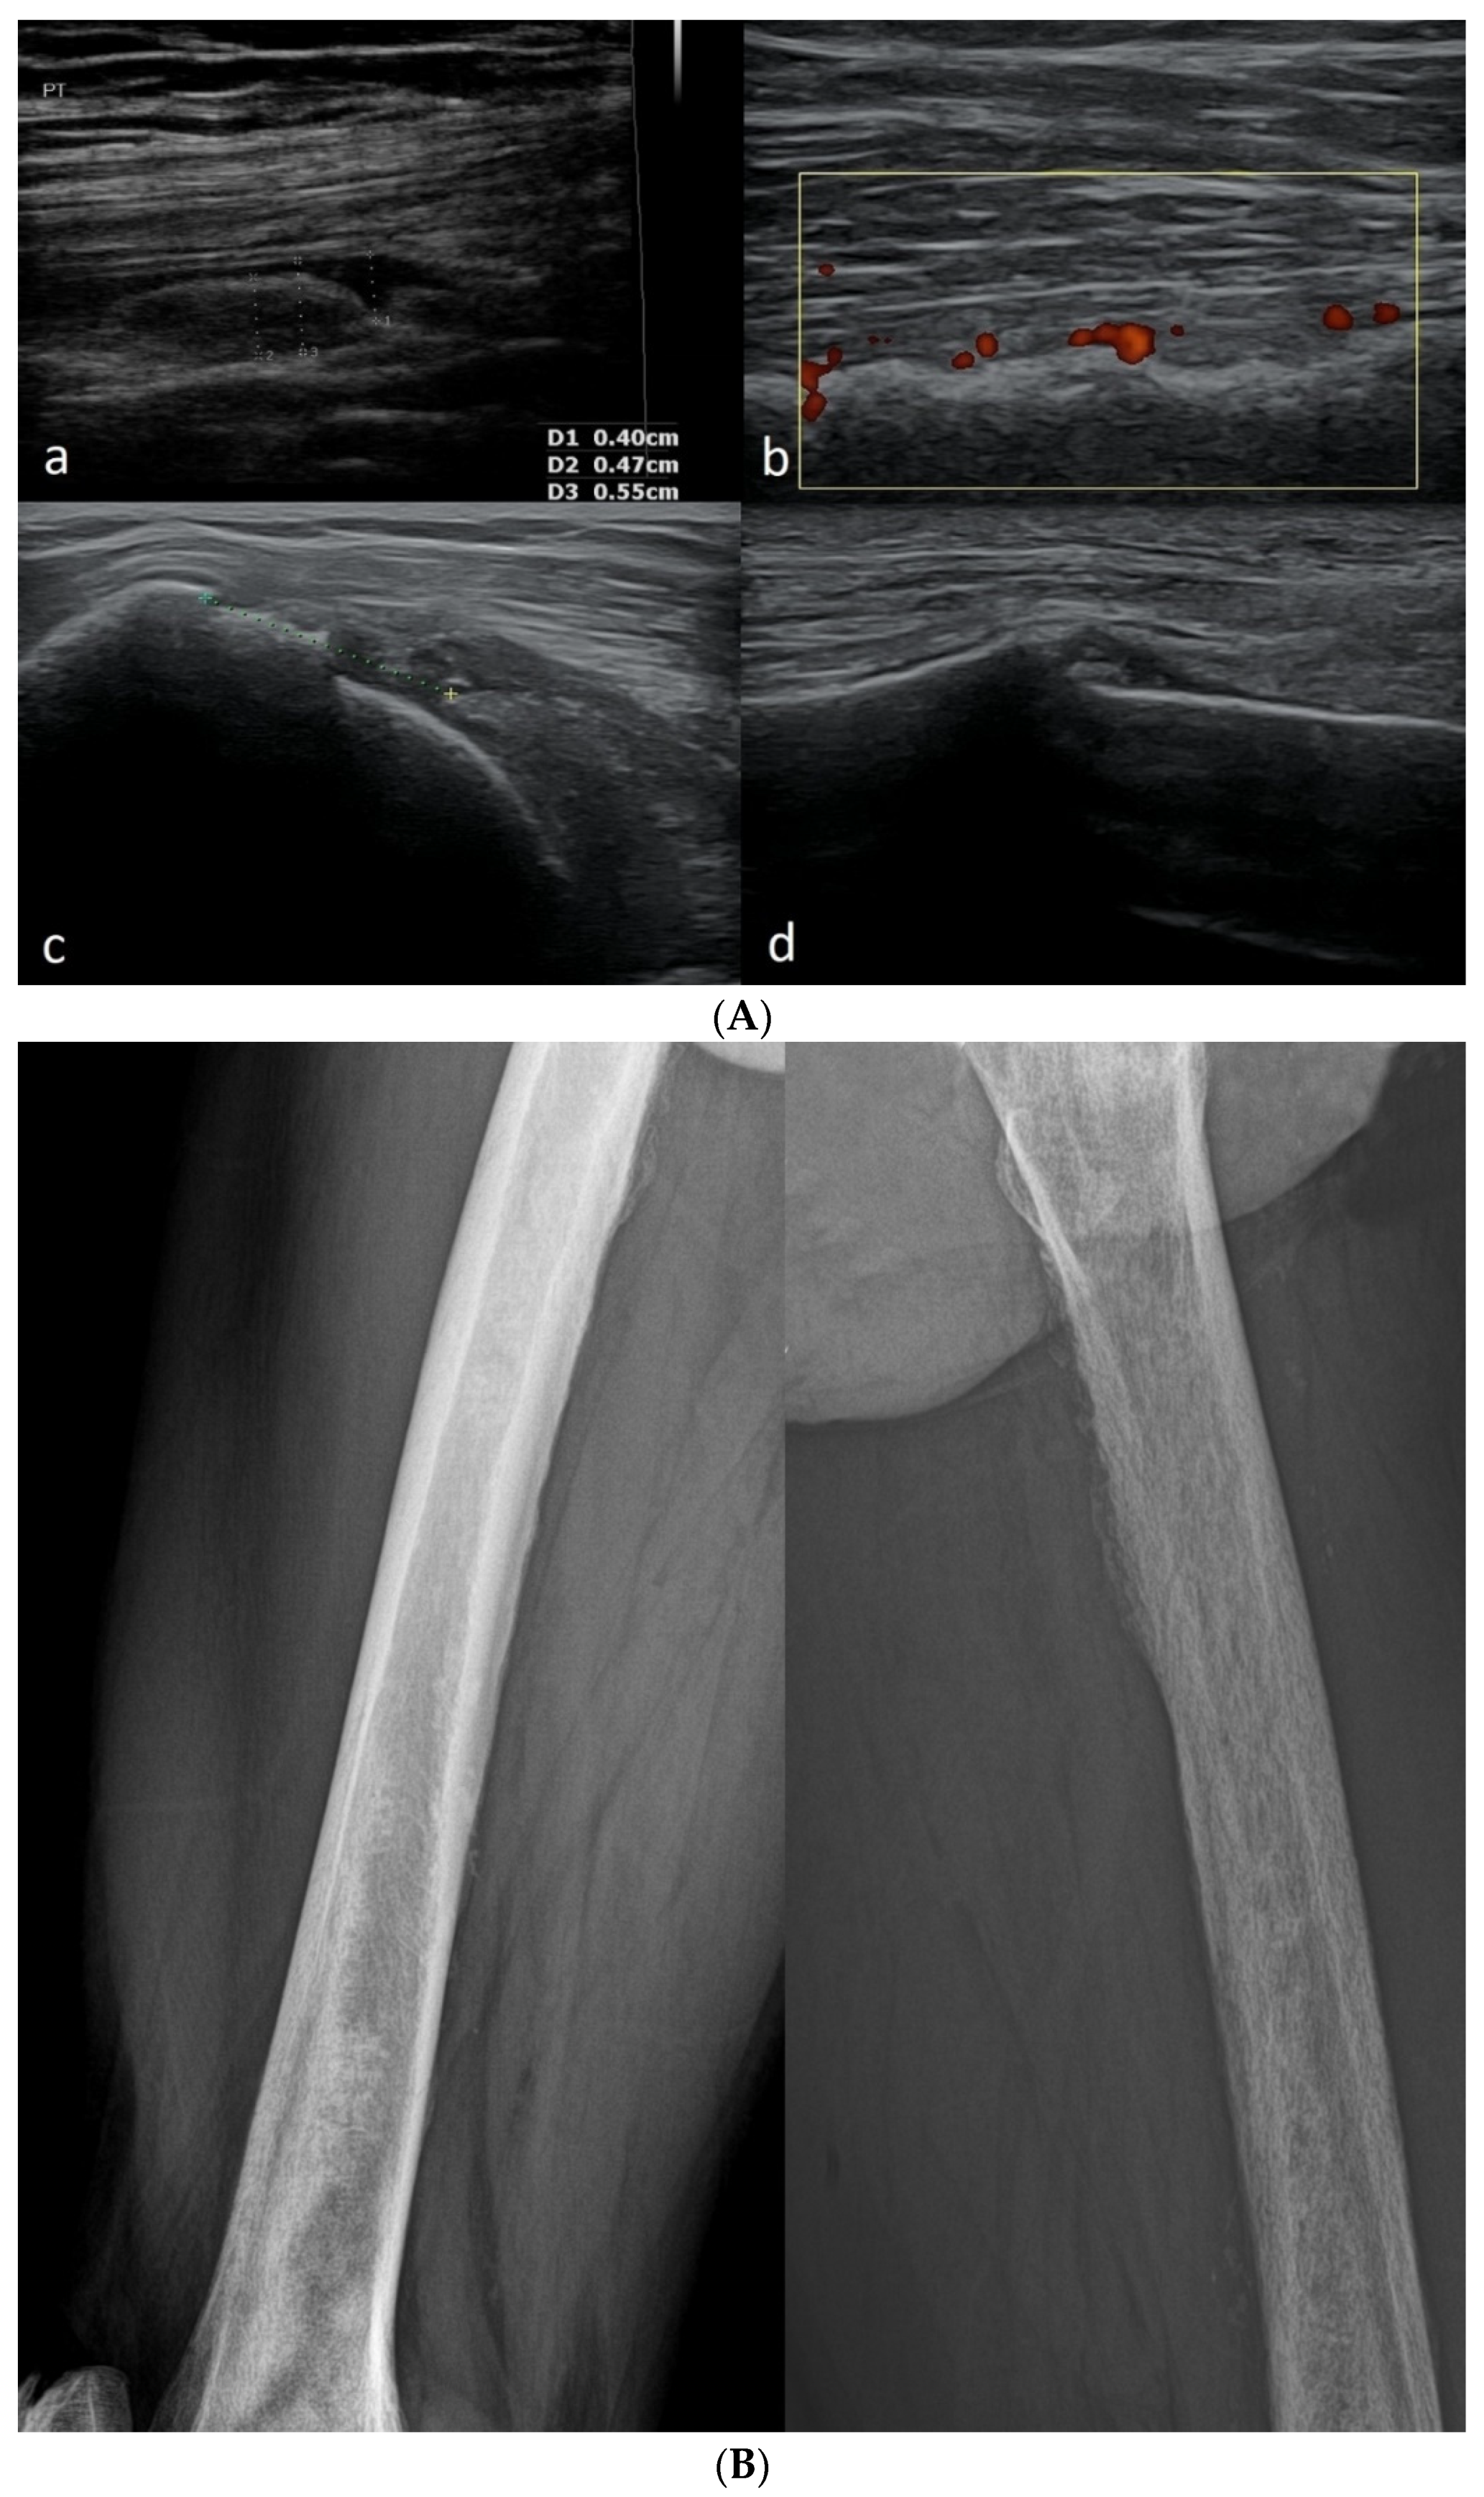

3.2.2. Osgood–Schlatter Disease

- Ladenhauf, H.N.; Seitlinger, G.; Green, D.W. Osgood-Schlatter disease: A 2020 update of a common knee conditio in children. Curr. Opin. Pediatr. 2020, 32, 107–112. [Google Scholar] [CrossRef] [PubMed]

- Launay, F. Sports-related overuse injuries in children. Orthop. Traumatol. Surg. Res. 2015, 101, S139–S147. [Google Scholar] [CrossRef] [PubMed]

- Mital, M.A.; Matza, R.A.; Cohen, J. The so-called unresolved Osgood-Schlatter lesion: A concept based on fifteen surgically treated lesions. J. Bone Jt. Surg. Am. 1980, 62, 732–739. [Google Scholar] [CrossRef] [PubMed]

- Ogden, J.A.; Southwick, W.O. Osgood-Schlatter’s disease and tibial tuberosity development. Clin. Orthop. Relat. Res. 1976, 116, 180–189. [Google Scholar]

- Hirano, A.; Fukubayashi, T.; Ishii, T.; Ochiai, N. Magnetic resonance imaging of Osgood-Schlatter disease: The course of the disease. Skeletal. Radiol. 2002, 31, 334–342. [Google Scholar] [CrossRef] [PubMed]

- Gholve, P.A.; Scher, D.M.; Khakharia, S.; Widmann, R.F.; Green, D.W. Osgood Schlatter syndrome. Curr. Opin. Pediatr. 2007, 19, 44–50. [Google Scholar] [CrossRef] [PubMed]

- Kujala, U.M.; Kvist, M.; Heinonen, O. Osgood-Schlatter’s disease in adolescent athletes. Retrospective study of incidence and duration. Am. J. Sports Med. 1985, 13, 236–241. [Google Scholar] [CrossRef]